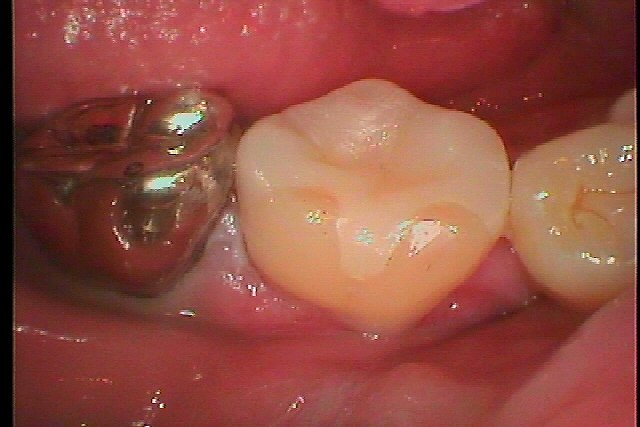

右下6番になります

この歯を白いセラミックを入れていきます

深い虫歯を除去していきました

白いきれいなセラミックにて修復していきました